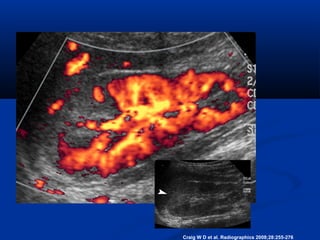

Focal

Hypoechoic area on Power

Doppler

• #9 Figure 3b.  Acute bacterial pyelonephritis. (a) US scan shows a wedge-shaped hyperechoic focus (arrowhead) in the upper pole of the right kidney related to acute bacterial pyelonephritis. (b) Color flow US image demonstrates diminished flow through the involved area.